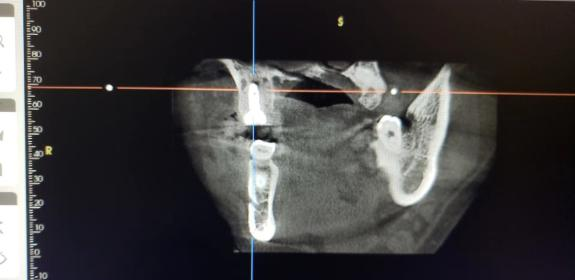

CBCT显示,右上六冠根折裂至髓室底

CBCT显示右上六冠根折裂至髓室底